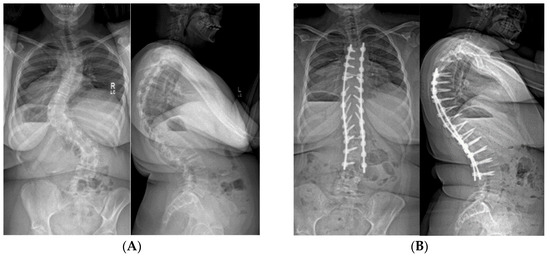

The most common complication affecting outcomes of spinal instrumentation is adding-on of the curve above or below the construct, usually as proximal or distal junctional kyphosis (PJK and DJK, respectively); PJK being the most frequent problem (Figure 6 and Figure 7). Patients with PWS characteristically have a “head forward” posture with their C7 vertebral plumb line falling much farther anterior to the sacrum than would be seen in a typically developed person [11,13]. This occurs by a combination of flattened cervical lordosis and/or thoracic hyperkyphosis. In fact, most PWS curves are kyphoscoliotic rather than the lordoscoloisis seen in idiopathic scoliosis cases. If the sagittal alignment is “anatomically” corrected surgically, patients often will compensate by increasing kyphosis, leading to hypolordosis or even kyphosis in the cervical spine, PJK and DJK [9,41]. In addition, up to 62% of patients with PWS have low bone mineral density and other musculoskeletal manifestations [11,42,43,44,45,46]. The combination of the PJK/DJK and bone weakness leads to a rate of hardware pull out/failure/rod fracture between 17% and 31% [9,40,41,47,48]. The consequences can be catastrophic [49].

Figure 6.

(A) 10-year-old female with PWS UPD type with 85° kyphosis, a 66° right thoracic and 61° left thoracolumbar curve. (B) Expandable, magnetically actuated rods are implanted from T2–L3, reducing her scoliotic curves to 25° or less, and her kyphosis to 48°. (C) 6 months post-operatively with developing proximal junctional kyphosis. Kyphosis now measures 81°.

Figure 7.

(A) 11-year-old female with PWS UPD type with 70° scoliosis, and 60° kyphosis. (B) Same patient at 12 years of age, after T2–L2 posterior spinal fusion. Overall kyphosis measures 50°. (C) Same patient at 3 years post-operatively with 60° distal junctional kyphosis.